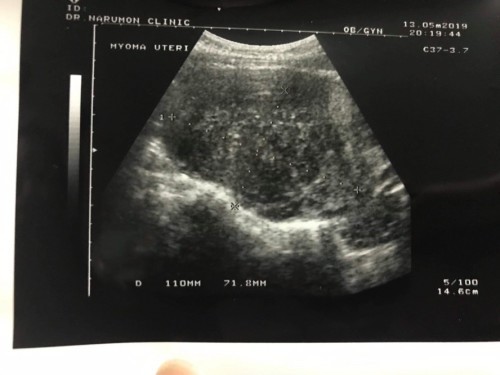

ตอนนี้ท้องได้ 5 สัปดาห์แล้วค่ะ แต่ไปซาวด์พบก้อนเนิ้องอก 10 เซน!!

แต่ไม่พบถุงน้ำดี หมอนัดมาซาวด์อีกที 8 week คือเครียดมากเลยค่ะ ตรวจปัสสาวะ 3 ครั้งขึ้นสองขีดหมดเลย กลัวว่าเนื้องอกจะมีผลทำไม่เห็นน้อง!!! ใครมมีคำแนะนำบ้างค่พ

เราก็ตรวจพบเนื้องอกในมดลูก5เซนค่ะและซิสต์ ตอนนี้ท้องได้จะ8เดือนล่ะค่ะ(ตอนนี้เนื้องงอกลดขนาดลงมาเหลือ4.3เซน) งดพวกถั่วเหลืองนะคะ ของคุณแม่ขนาดใหญ่อาจมีผลต่อเด็กเพราะจะเบียดการเจริญเติบโตของเด็กในครรภ์ หรือหมออาจจะแนะนำให้ยุติการตั้งครรภ์ค่ะ เป็นกำลังใจให้ค่ะ สู้ๆๆๆ

พบหมออย่างใกล้ชิดนะคะ ถ้าท้องจริงความเสี่ยงค่อนข้างสูง เคยมีเพื่อนท้องและมีเนื้องอกในมดลูกขนาด 8เซนฯ เนื้องอกกับลูกฝังตัวตรงข้ามกันเลย มดลูกขยายตัวได้ไม่เยอะทำให้ลูกตัวเล็ก ลูกออกมาปกติดี ตอนนี้อายุ 12ปีแล้วค่ะ เป็นกำลังใจให้นะคะ